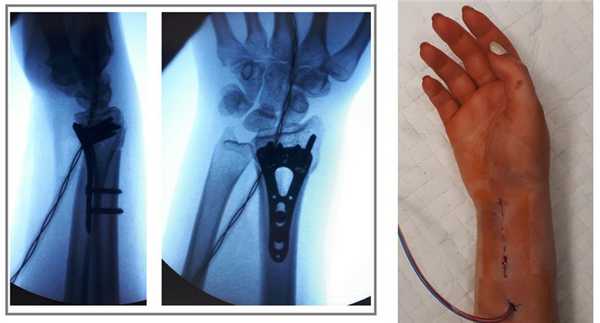

В случаях оскольчатых переломов дистального метафиза лучевой кости со значительным смещением рекомендуется использовать активный вакуумный дренаж. Это позволяет снизить давление в сгибательном компартменте, уменьшает отёк и пропитывание тканей кровью, и предотвращает развитие КРБС (комплексного регионарного болевого синдрома). Также для профилактики КРБС рекомендуется использование витамина С в дозе 200 мг\сут до 45 дней после травмы. Локальная криотерапия, хивамат, магнит, возвышенное положение конечности, способствуют уменьшению отёка и позволяют раньше приступить к реабилитационным мероприятиям.

Функция конечности через 3 недели после остеосинтеза.

Такая фиксация даже при таких тяжёлых дистальных переломах позволяет начать раннюю активизацию, занятия лечебной физкультурой в кратчайшие сроки после операции. Для профилактики КРБС при тяжёлых оскольчатых переломах рекомендуется использование витамина С в дозе 200 мг в сутки до 45 дней после травмы, возвышенное положение конечности в покое, хивамат, гипербарическая оксигенация, использование таких препаратов как актовегин и трентал.